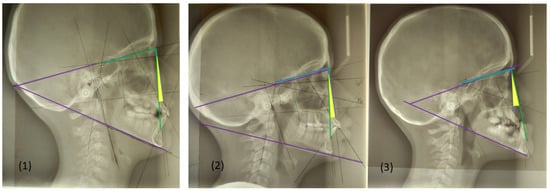

- SNA angle is formed between points of center sella turcica (S) and nasion (N) as the most anterior point of frontonasal suture, and subspinal point of deepest spot of contour of premaxiila (A), which presents the position of maxilla anteriorly or posteriorly to the cranial base. An average value of SNA angle is 80° ± 2°, while a higher value shows that the maxilla is protrusive, and a lower value indicates that the maxilla is more retrusive than normal;

- SNB angle is formed by connecting points of center sella turcica (S) and nasion (N) as the most anterior point of frontonasal suture, and the point that presents the deepest spot of the mandible (B). The average value of SNB is 78° ± 2°. A value above indicates that the mandible is more anterior to the cranial base, or protrusive, and a value below is a more backward, retrusive position;

- ANB angle is the angle between point A-N-B or the difference between SNA and SNB angle, with a normal discrepancy between maxilla and mandible ± 2°. A higher value points to the angle class II malocclusion relationship, while a lower angle indicates the angle class III malocclusion (Figure 2).